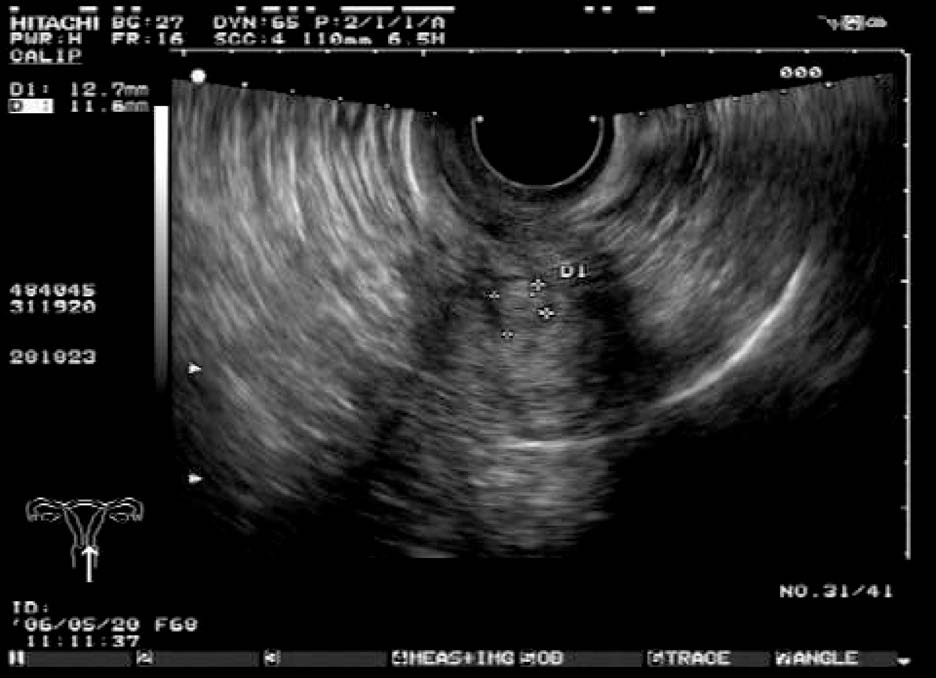

2. 肌壁间肌瘤

多呈低回声,大小不一,包膜完整,瘤体与宫壁正常肌层间界限清晰,周围显示环状彩色血流信号。肌瘤较大时,可压迫和推挤宫腔,使宫腔内膜回声移位或变形。

患者,女,42岁,常规体检。超声检查声像图显示:子宫前位,三径正常,边界清,子宫内膜欠清。肌内可见多个低回声包块,较大者约1.7cm×1.4cm(前壁)、1.8cm×1.4cm(前壁)、1.9cm×1.4cm(后壁),边界清,有假包膜,内部回声均匀,子宫边界规整。CDFI探查:较大团块周围见半环状彩色血流信号。包块内未见彩色血流信号。宫腔内可见节育器影像,距宫底约1.5cm。

超声提示:子宫肌瘤(肌间);宫内节育器,位置正常。